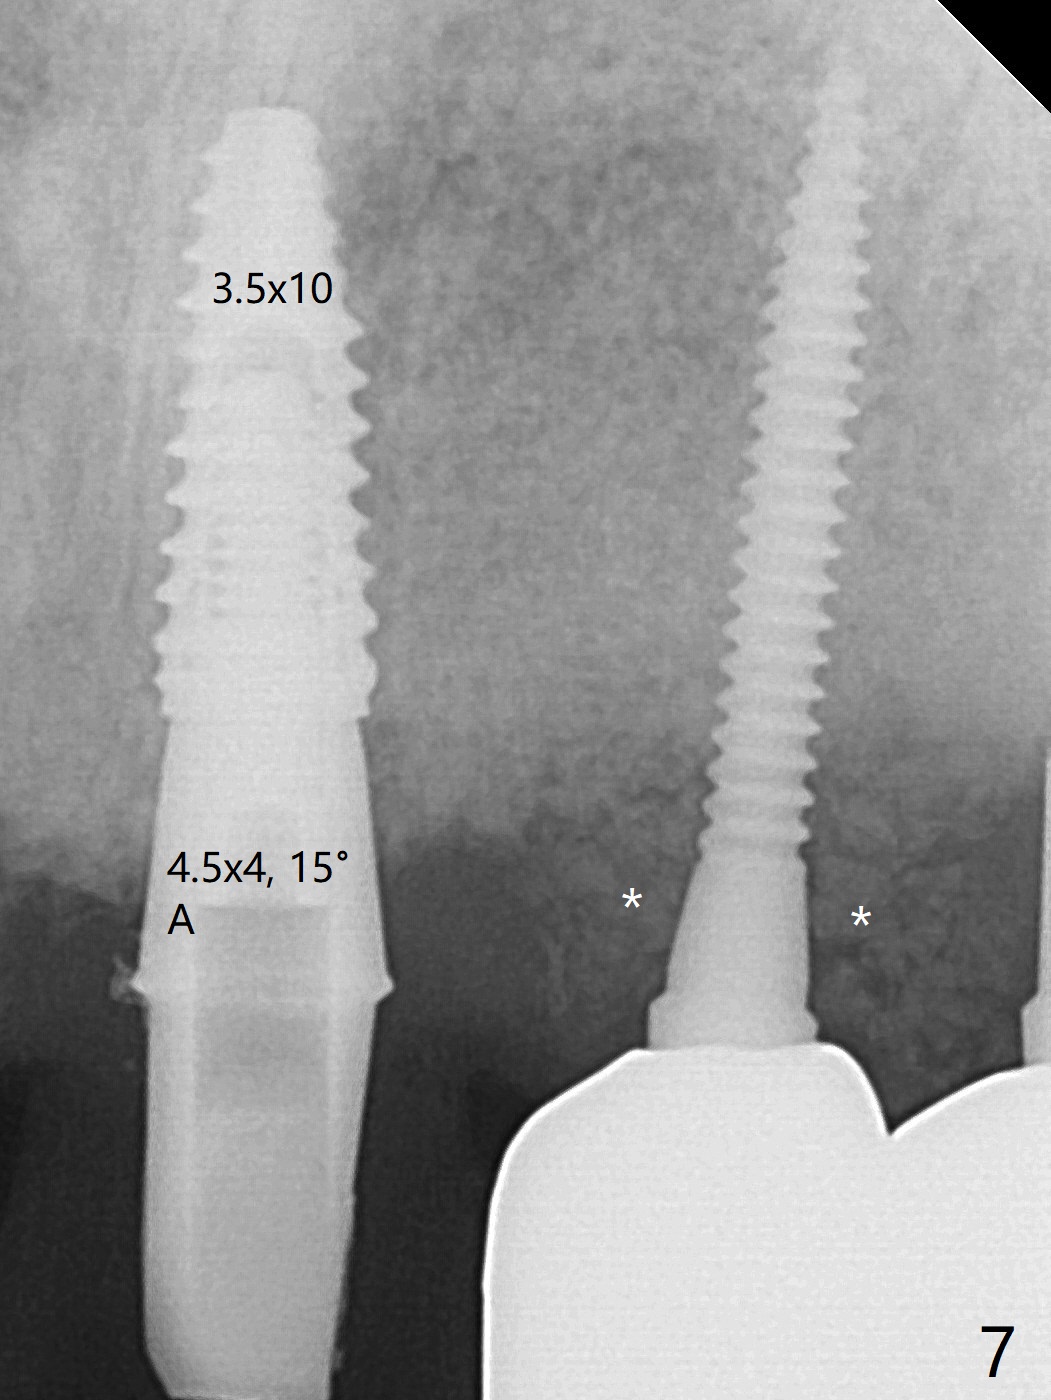

The implant access at #9 closes 1 week post implant fracture (Fig.1,4). There is mild gingival erythema at #10 (Fig.2,3 ^). There is bone around the fractured implant, which is palatally placed (Fig.5). The 2 mm implant is removed using 2/3 mm trephine bur. In spite of moving the osteotomy buccally, a 4.5x4 mm, 15 degree A-type angled abutment is installed for an immediate provisional following placement of a 3.5x10 mm implant (Fig.7, 25 Ncm). Sticky bone is placed (Fig.7 *) palatal to the implants at #9 and 10 (with thread exposure, Fig.6). While the majority of periodontal dressing remains in place (Fig.9,10), the suture in the exposed area appears to hold the papilla in place (Fig.8 <). Herpetic infection develops in the palate (Fig.9). Two months later, the gingiva at #10 is healthy; it appears that the implant threads are covered by bone graft. The immediate provisional (fabricated before suture) keeps the gingiva in an ideal position for impression of final restoration. It appears that the access hole is in a right area for screw retained restoration. The gingival cuff is healthy immediate pre-cementation, 4 months postop (Fig.12,13). The lab does not make access hole for the final crown (Fig.14). The implant remains subcrestal 4 months postop (Fig.15). Since the shade of the crown is off, the abutment remains un-torqued and the crown is cemented with temp bond. The implant threads at #10 seem to be covered by bone graft 4 months postop (Fig.16).